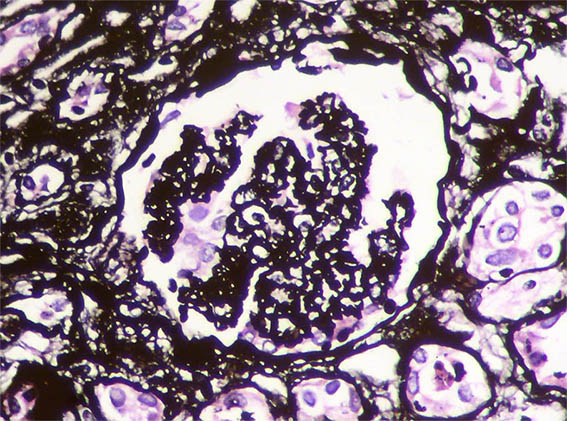

Figure 8. Methenamine-silver stain, X100.